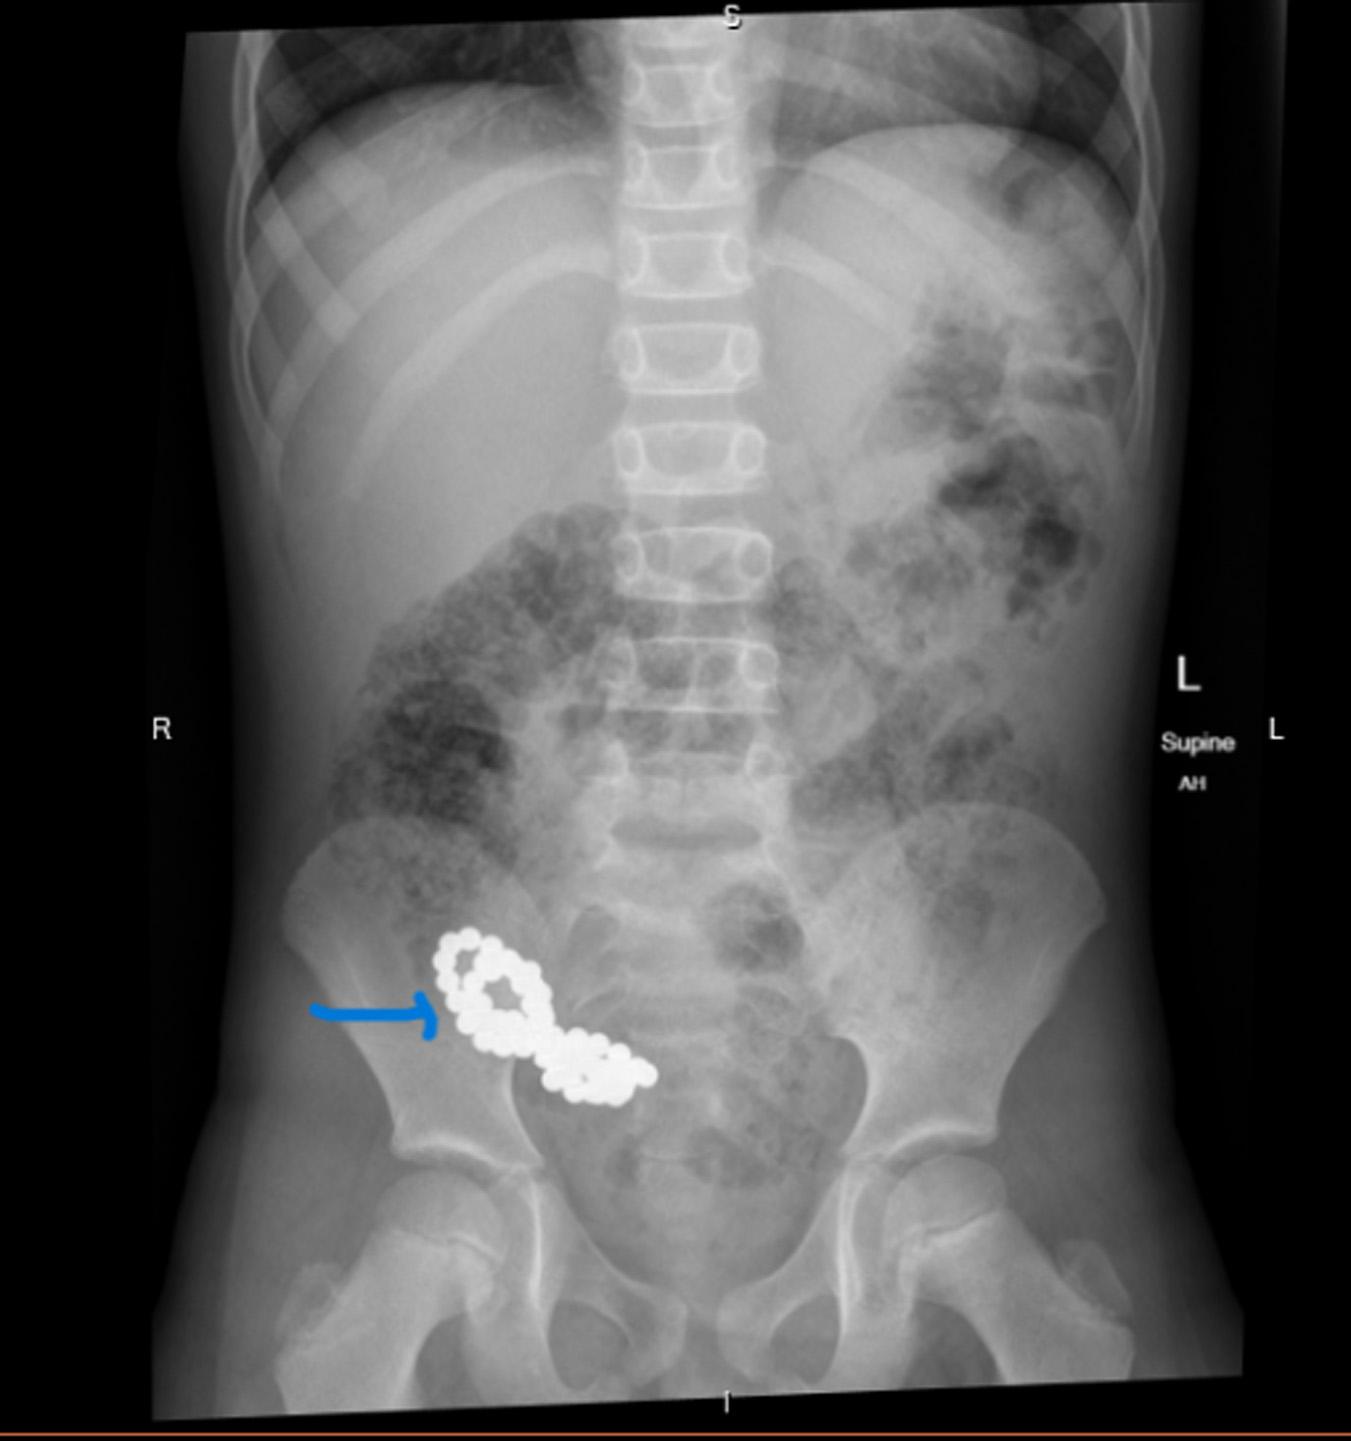

Image. Computedtomographyabdomenwithintravenouscontrast demonstratingdilated, fluid-filledloopsofsmallbowelandapattern ofswirlingmesentericvesselscalledthewhirlpoolsign(arrow).

Onpresentationthepatientwasinnoacutedistressbut wasclammyandtachycardicatarateof118beatsper minute.Onexam,herabdomenwasdiffuselytenderwithout distentionorperitonealsigns.Shehadanelevatedwhite bloodcellcountat17 × 103 permicroliter(K/μL)(reference range4.5–11.0K/μL),anINRof5.5,andalacticacidof 3.7millimolesperliter(mmol/L)(0.4–2.0mmol/L).An abdomenandpelvisCTwithintravenous(IV)contrast showed findingssuspiciousforclosedloop,smallbowel obstruction.TheCTalsodemonstratedevidenceofswirling ofthemesentericroot,knownasawhirlpoolsign(Image, Video).The findingsofthewhirlpoolsignonCTsuggested mesentericvolvulusasthecauseofherbowelobstructionand promptedemergentsurgicalconsultation.

pathology.However,radiographsareofteninconclusivein midgutvolvulusbecauseevenapositive “doublebubble” signindicatingasmallbowelobstructiondoesnotruleouta concomitantmidgutvolvulus.7 Computedtomographywith IVcontrastgivesmuchgreaterdetailoftheabdomenandcan provideevidencesuggestiveofamidgutvolvulus.ClassicCT imaging findingsincludeawhirlpoolsignoftwisted mesentery,malrotatedbowelconfiguration,inverted superiormesentericarteryandsuperiormesentericvein relationship,bowelobstruction,andfree fluid/freegasin advancedcases.8 ThewhirlpoolsignseenonCTrepresents themesenteryandsuperiormesentericveinwrapping aroundthesuperiormesentericarteryina counterclockwisedirection.